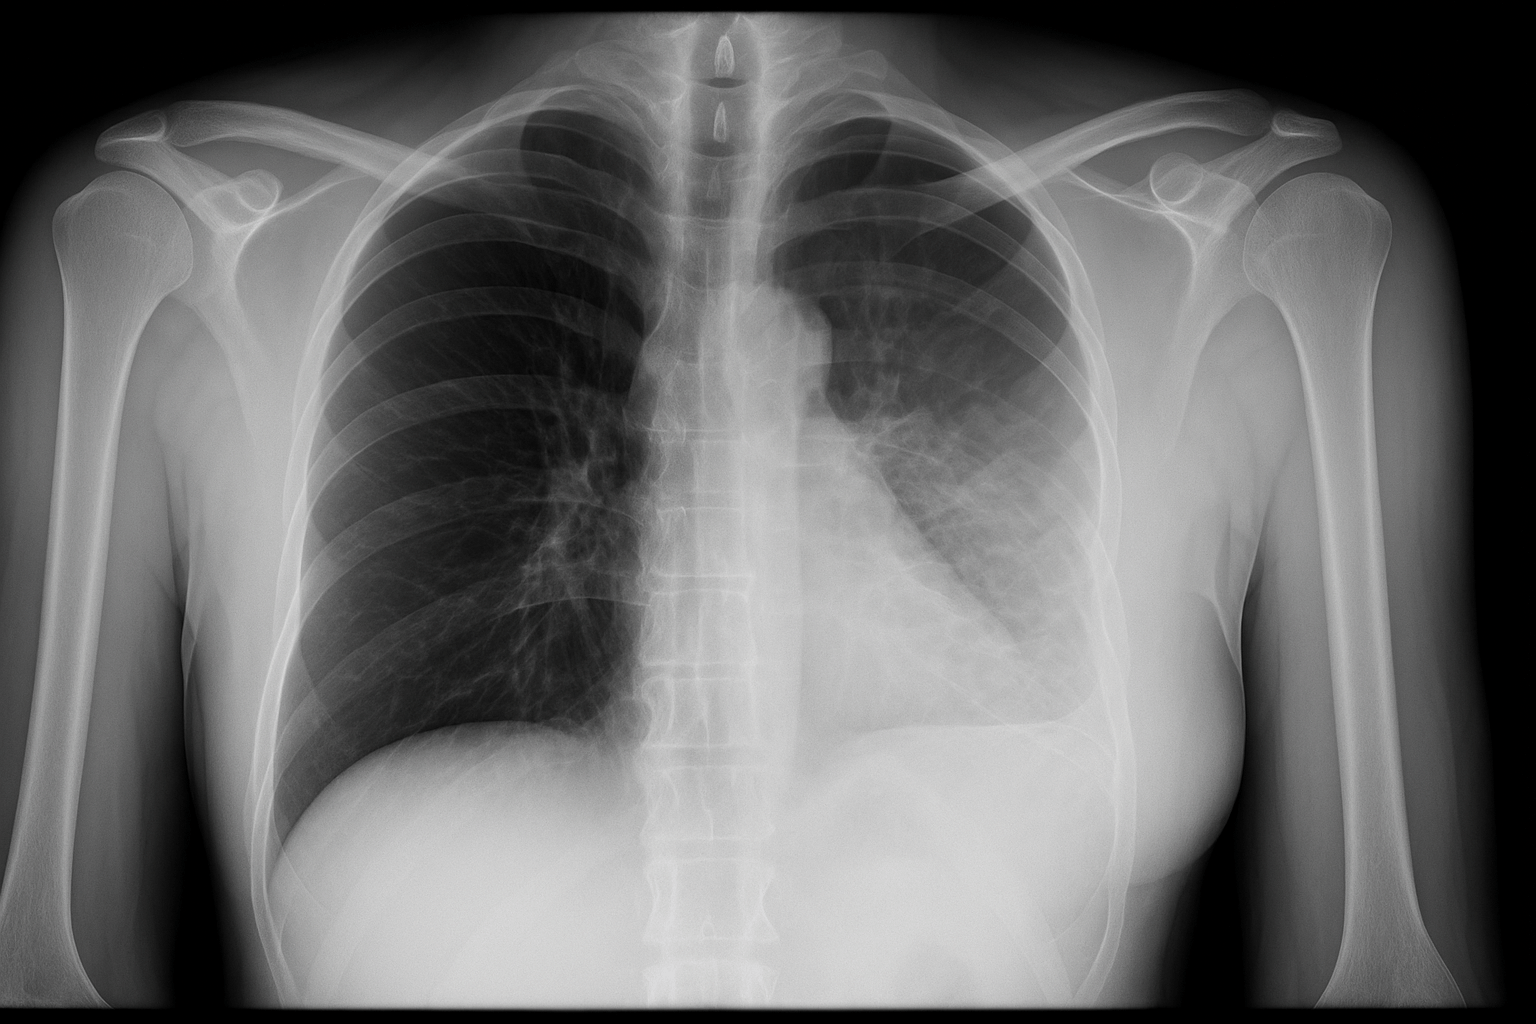

Melhora da respiração

Exercícios respiratórios orientados ajudam a fortalecer a musculatura e facilitar a expansão dos pulmões depois da cirurgia — especialmente importantes para quem já tem alguma condição pulmonar prévia. Além disso, a fisioterapia pré-operatória vai ajudar o paciente a ter uma melhor percepção de sua respiração e maior consciência corporal. Isso é extremamente útil no pós-operatório, pois o paciente já está relativamente “treinado” para realizar os exercícios.

2. Fisioterapia respiratória antes da cirurgia

Em alguns casos, iniciar sessões de fisioterapia antes do procedimento pode ajudar muito. Os objetivos incluem:

- Melhor eliminação de secreções;

- Fortalecimento dos músculos usados na respiração;

- Treinamento de técnicas para facilitar a expansão pulmonar.

A fisioterapia respiratória é obrigatória antes da cirurgia torácica?

Não é obrigatória em todos os casos, mas pode ser recomendada para fortalecer a musculatura respiratória e prevenir complicações no pós-operatório.